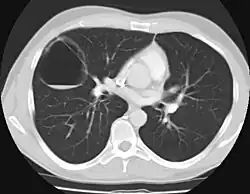

CPAM on chest radiograph in a newborn. Large cystic changes in the left lung, leading to a mediastinal shift to the right due to their mass effect.